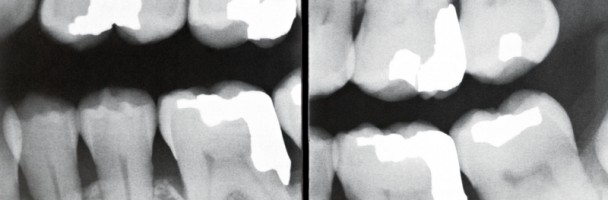

Il Full radiografico endorale è l’esame radiografico più indicato ad individuare patologie paradontali, perchè mette in risalto ed in dettaglio quei problemi che possono sussistere a carico della gengiva e degli altri tessuti parodontali e che avvolte l’esame ortopanoramico non evidenzia. Consiste in un insieme di radiografie che forniscono un’immagine chiara e minuziosa dell’architettura ossea che circonda i denti. Da queste radiografie si deduce fedelmente l’entità della degenerazione dei tessuti duri del parodonto e la perdita di attacco connettivale.

La malattia parodontale o piorrea è una patologia a carico delle strutture di sostegno del dente  e cioè gengiva, osso alveolare, cemento e legamento parodontale. Nella sua forma iniziale e reversibile, la gengivite, sono interessati i tessuti parodontali marginali, la gengiva, e non ci sono problemi di attacco del dente. Sintomi clinici principali sono l’edema, l’arrossamento dei margini e il sanguinamento. L’evoluzione irreversibile della patologia, la parodontite, riguarda i tessuti parodontali più profondi (osso, cemento, legamento parodontale) ed è contraddistinta dalla perdita di attacco del dente. Le malattie parodontali, se non trattate, possono produrre danni anche in organi distanti dalla bocca, quali cuore e polmoni.